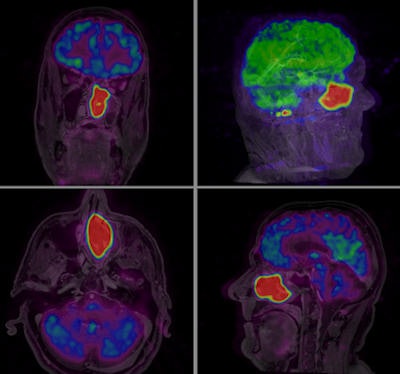

B-cell lymphoma of the left sinus with no metastatic disease. PET/MR images are shown in all three imaging planes for a clear picture of pathology in a very critical nasal cavity area. Ingenuity TF PET/MR system was used. All images and chart courtesy of Philips Healthcare.Of all 20 tumor locations, 17 tumors were detected with PET and MRI. Two tumors would have been missed with FDG-PET, and three tumors would have been missed by MRI. In five patients, additional lymph nodes that were suspicious for metastases were detected by FDG-PET. PET tumor detectability in the head and neck region increased on the late imaging on the PET-MR system, which was due to the increased tumor contrast at a later imaging time point and the higher resolution of the new device. Although a direct comparison of standard uptake values (SUV) of a different PET scanner is not valid, in parallel to the increased qualitative detectability, at late timepoints an increase of SUVmax values of the tumors was seen, according to the Dresden team.

A total of 17 patients (10 men, seven women, mean age 38) were examined using a Philips Ingenuity TF PET/MR system. The device consists of two separate machines linked through a single patient table, allowing sequential imaging. Standard imaging protocols of both modalities were combined.

In all cases, diagnostic quality images were obtained for both modalities in a single session. A total of 13 subjects had positive findings, which were confirmed by clinical follow-up in seven cases. One false positive PET uptake was due to radionecrosis. The remaining five positive subjects showed metabolic changes, the interpretation of which is currently under evaluation with clinical follow-up (e.g., global cortical hypometabolism and basal ganglia hypermetabolism in a case of obsessive compulsive disorder). Of the four negative studies, no false negatives were identified with clinical follow-up.